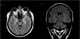

Neuroacanthocytosis

Neuroacanthocytosis is a label applied to several genetic neurological conditions in which the blood contains misshapen, spiculated red blood cells called acanthocytes. The 'core' neuroacanthocytosis syndromes, in which acanthocytes are a typical feature, are chorea acanthocytosis and McLeod syndrome. [Source: Wikipedia ]